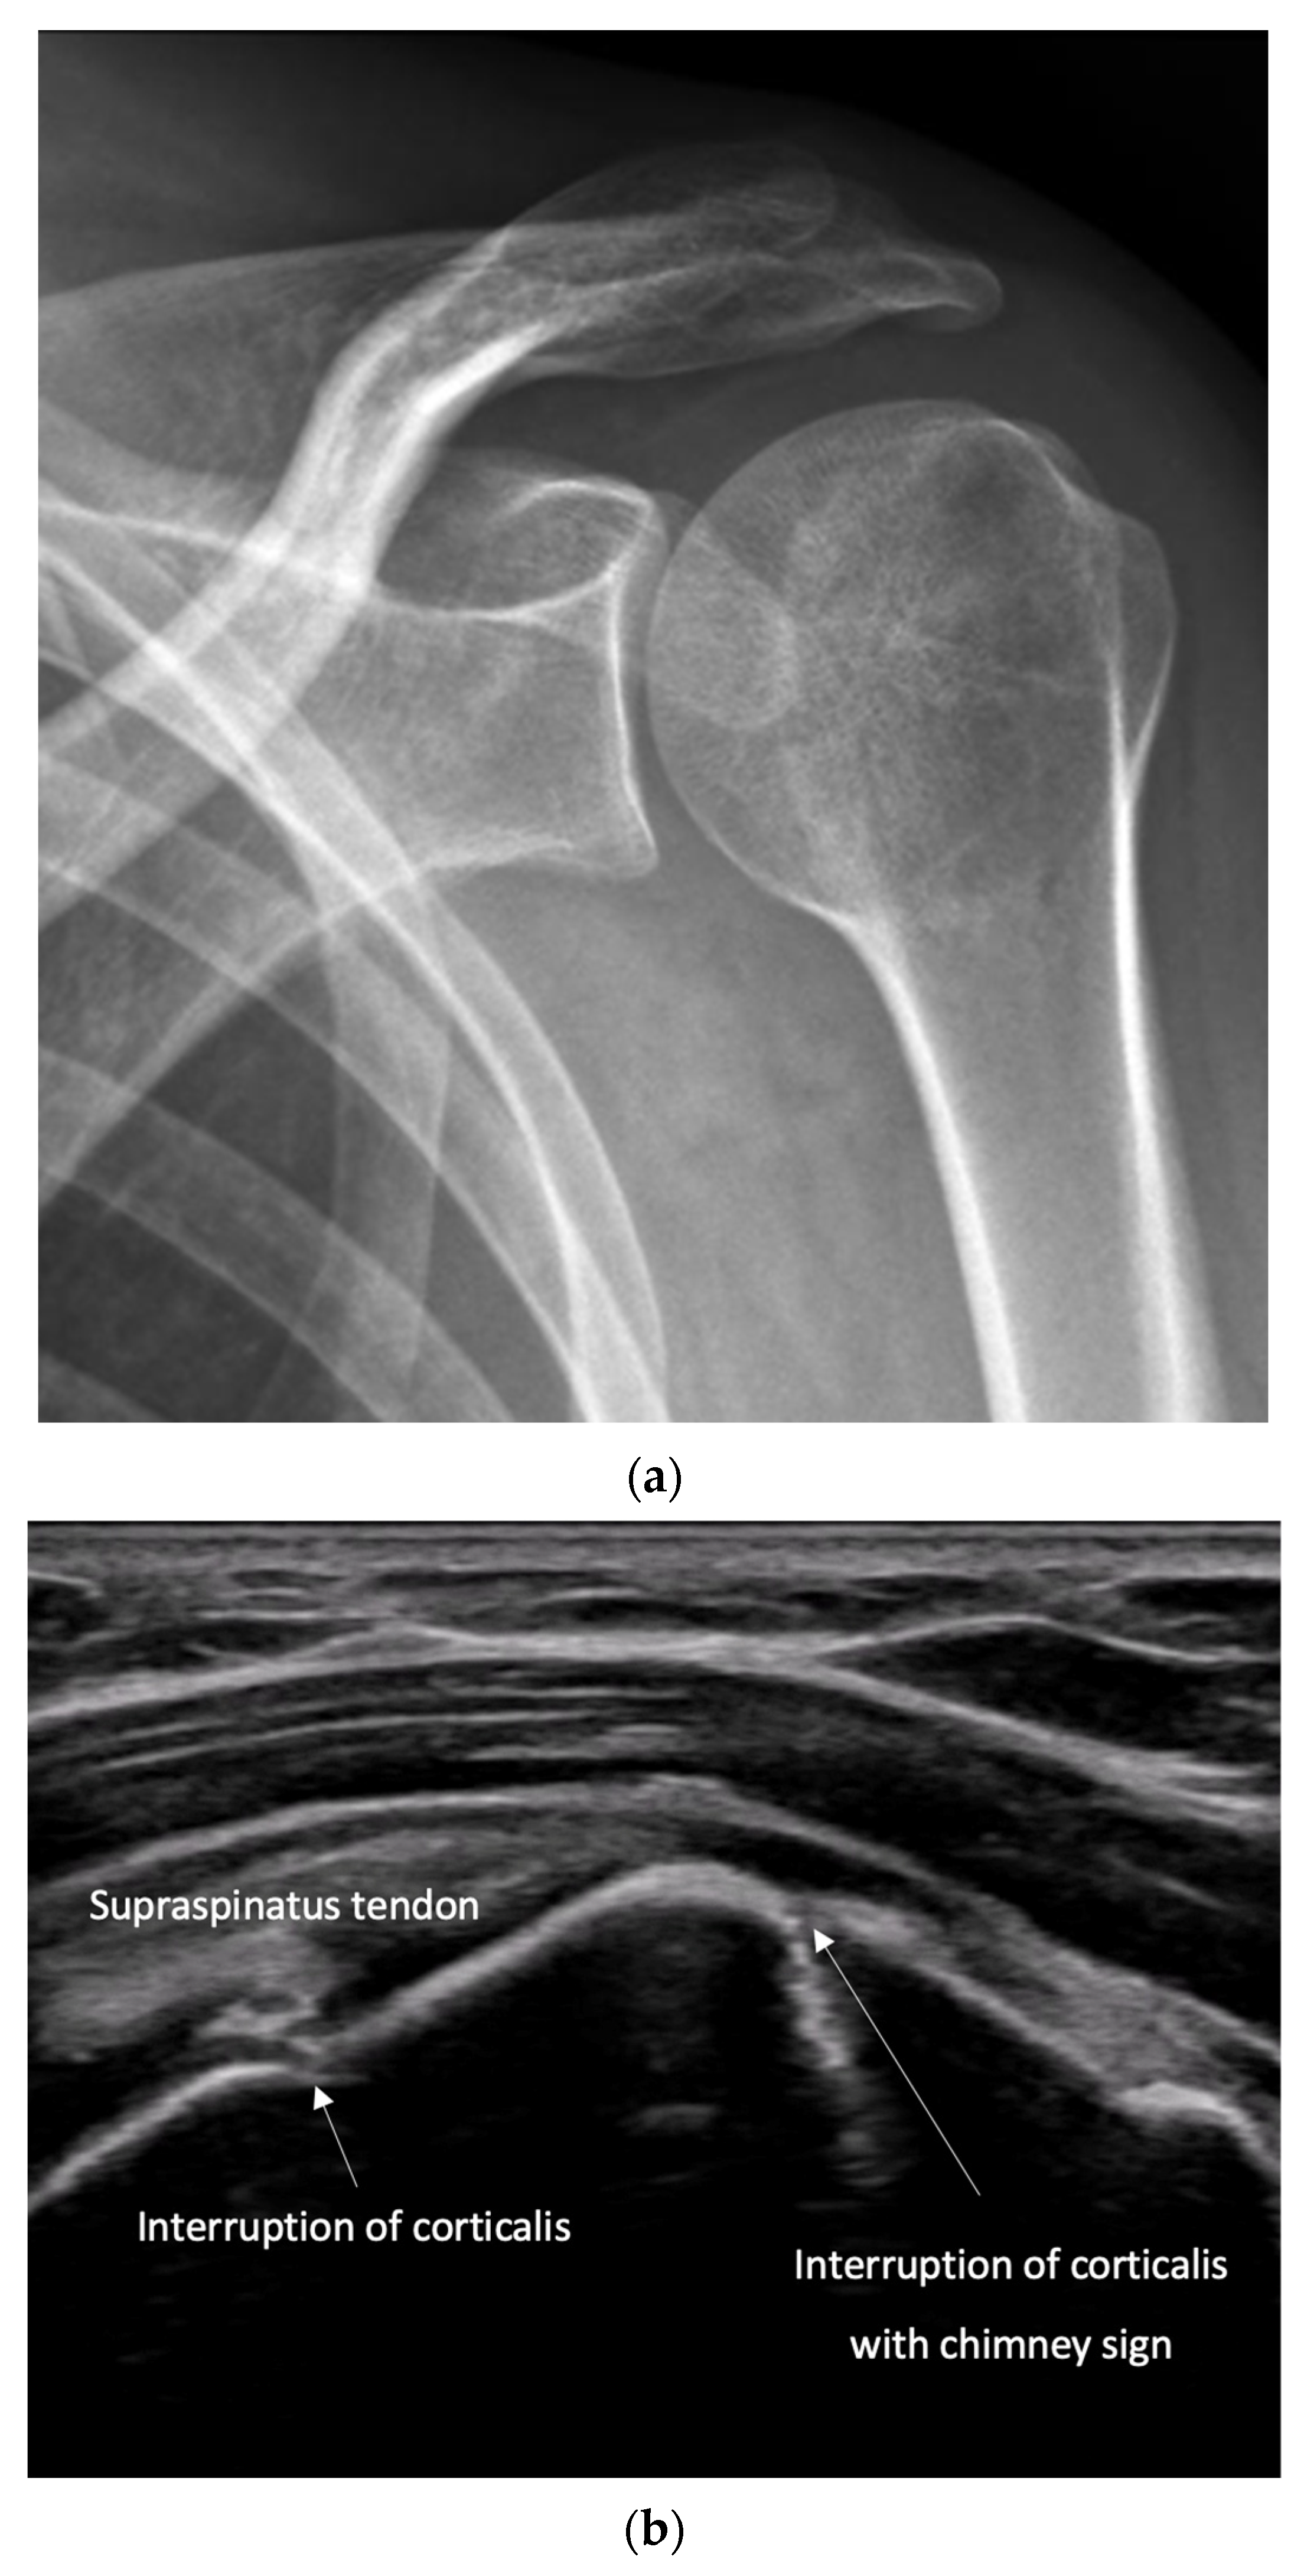

4.2. Sonoanatomy of Fractures [Figure 5, Figure 6, Figure 7 and Figure 8]

- Irregularity, interruption, or gaps in the cortical line: the cortical bone normally appears as a continuous, bright echogenic line, which is interrupted or irregular in the presence of a fracture.

- Reverberation artifacts within or adjacent to the fracture gap (also known as the “chimney sign”): these repetitive echoes are caused by ultrasound waves reflecting off the fracture surfaces.

- Quick exclusion of fractures in shoulder dislocations for timely reduction (Figure 13).

- Recommendation 6: Ultrasound should be integrated into the assessment and management of shoulder injuries, including proximal humerus fractures, shoulder dislocations, and post-relocation maneuvers, both prehospitally, in emergency departments, and other acute care settings.

- Example: Suspected left shoulder dislocation